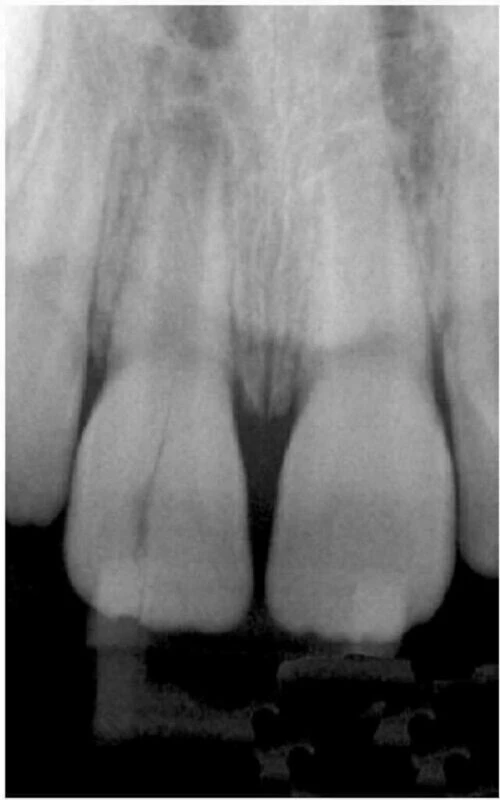

Hình 1. Phục hồi trong thân răng không khít sát có thể tạo áp lực lên răng và gây nứt dọc chân răng.